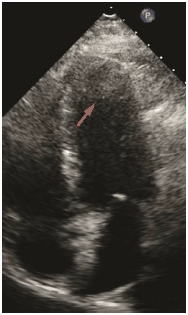

Marque a alternativa que apresenta o artefato representado na imagem abaixo (seta).

Provas